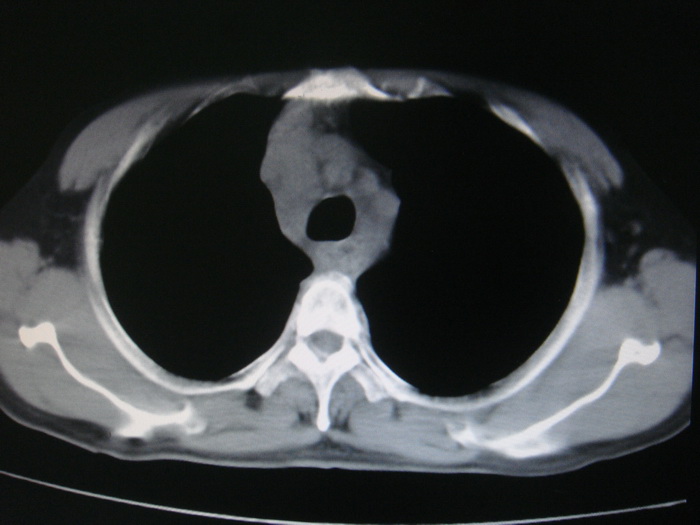

标题: CT28366:男性,45岁,偶尔发现右颈部肿块行胸部CT扫描。 [打印本页]

男性,45岁,偶尔发现右颈部肿块行胸部ct扫描。

两肺多发结节灶及纵膈淋巴结肿大考虑为转移

两肺多发性转移瘤,纵隔淋巴结转移。

两肺多发性转移瘤,纵隔淋巴结转移。食道中上段管壁似乎增厚,作相关检查。

两肺多发性转移瘤,前上纵隔淋巴结转移。